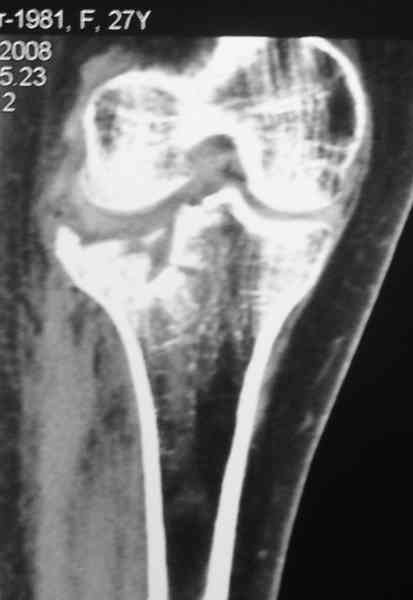

Уважаемый Абдурашид. Если нет противопоказаний , то из оперативных способов, я бы рекомендовал следующие: Полное замещение наружного мыщелка аллотрансплантатом либо открытая репозиция с элевацией и замещение дефекта ауто или аллокостью. В Ваших условиях , я бы рекомендовал второй способ. Во-время элевации необходимо разъединить фрагменты со стороны сустава ( надсечь скальпелем по линиям перелома, а затем тонким остеотомом их разъединить. При помощи долота произвести неполную остеотомию ( захватите не менее 1,5 - 2 см губчатой кости и поднять фрагменты, визуально отрепонировать и фиксировать 2-3 спицами. Дефект заместить костным ауто или аллатрансплантатом. Окончательная стабилизация пластиной ( лучше с угловой стабильностью, либо АВФ - позволит спокойно устранить угловую деформацию.

Недавно поступила больная через 1,5- 2 месяца.